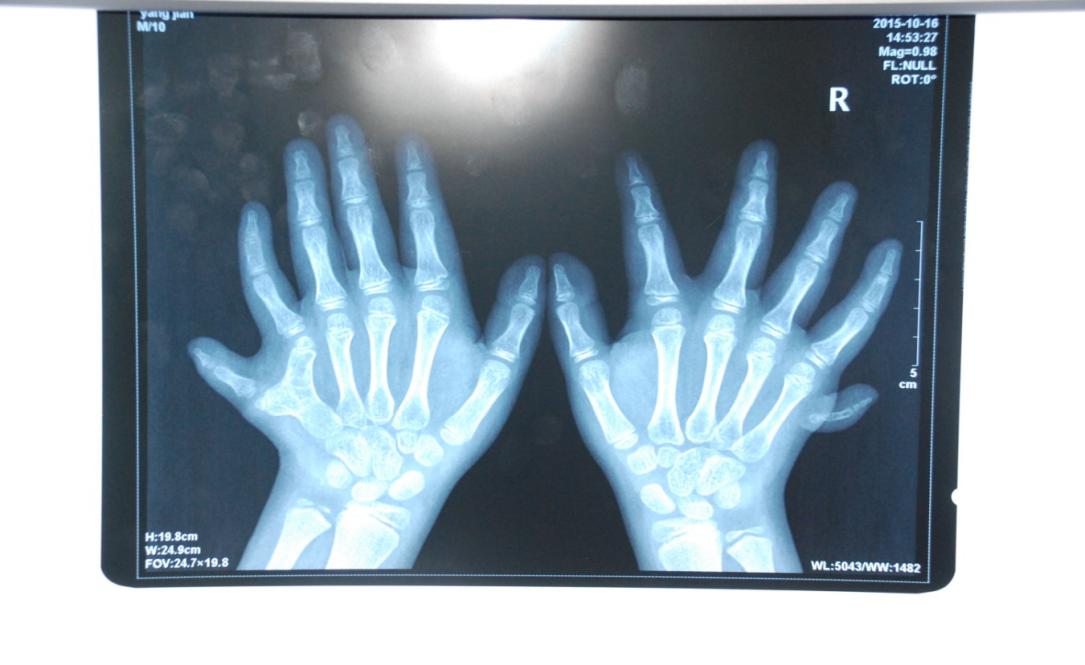

廈門眼科中心小兒眼科修陽(yáng)暉博士在日常的診療過(guò)程中就接診了不少這樣的的特殊家庭,讓其尤為印象深刻的就是一年前接診的BBS綜合征患者。當(dāng)時(shí)來(lái)院就診的是一對(duì)親兄弟,之前已在多家醫(yī)院做過(guò)檢查,因其均有較大散光和斜視,肉眼下眼底檢查未見(jiàn)異常,故外院均診斷為弱視,這也符合眼科門診常規(guī)的診斷邏輯與思維。但由于兄弟倆均有智力發(fā)育遲緩、特殊面容及四肢均有六指和六趾的特異體征引起了修陽(yáng)暉博士的警覺(jué):會(huì)不會(huì)是一種特殊遺傳性疾病或綜合征?后續(xù)的檢查結(jié)果進(jìn)一步證實(shí)了修陽(yáng)暉博士的懷疑---患兒均有夜盲,ERG、VEP及OCT檢查顯示雙眼的視網(wǎng)膜神經(jīng)上皮層結(jié)構(gòu)及功能均明顯異常。由于之前未遇到此種病例,修陽(yáng)暉博士在診斷一欄寫下視網(wǎng)膜色素變性并打上了個(gè)問(wèn)號(hào),同時(shí)留下了病人的聯(lián)系方式。

BBS綜合征(Bardet-Biedl綜合征)是一種主要累及纖毛結(jié)構(gòu)與功能的罕見(jiàn)常染色體隱性遺傳性疾病。纖毛分布于哺乳動(dòng)物體內(nèi)的大多數(shù)細(xì)胞,它是一種廣泛存在于各種細(xì)胞表面的細(xì)胞器,體型微小但結(jié)構(gòu)復(fù)雜、作用強(qiáng)大,能感知細(xì)胞外機(jī)械和化學(xué)信號(hào)變化并協(xié)助其轉(zhuǎn)導(dǎo)到細(xì)胞內(nèi)部從而引起細(xì)胞應(yīng)答。高等動(dòng)物的視覺(jué)、觸覺(jué)、嗅覺(jué)、聽(tīng)覺(jué)的傳遞都依賴于體內(nèi)外正常的纖毛結(jié)構(gòu)和功能。因此BBS綜合征常累及全身多個(gè)系統(tǒng)和器官,在臨床上主要表現(xiàn)為:視網(wǎng)膜色素變性、智力發(fā)育異常、向心性肥胖、多指(趾)、性腺發(fā)育異常、腎臟異常。除此之外還有許多諸如:語(yǔ)言發(fā)育障礙、聽(tīng)力異常、嗅覺(jué)異常、斜視、白內(nèi)障、散光、牙齒發(fā)育異常、短指(趾)、并指(趾)、肝纖維化、糖尿病、高血壓等表現(xiàn)。